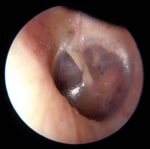

Review: Otoscopy Examples of Abnormal TMs

Normal Otoscopic Exam Findings:

• Tympanic membrane (TM) should be intact and

appear pearly grey or whitish/pinkish grey

Bulging, red TM - Acute Otitis Media Cholesteatoma

Normal TM – Right Side

Pars flaccida

Lateral/short process of malleus

Incus Manubrium of malleus

Umbo Otitis media with effusion Myringosclerosis

Cone of light

Pars tensa

Annulus

Hemotympanum Retracted TM

Back